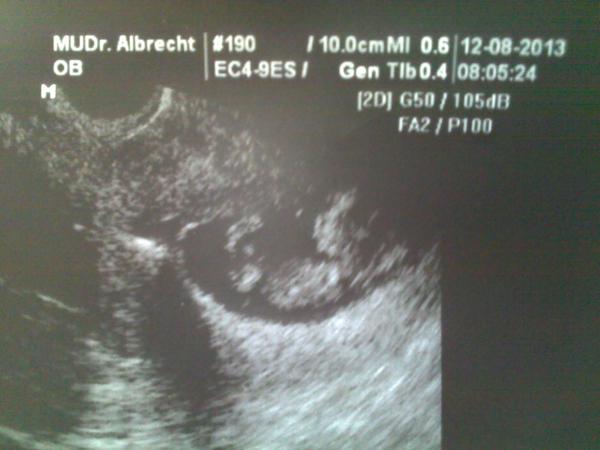

Ahojky @20petula89 Mám pro tebe svoji zkušenost. Jsem podruhé těhu přes tělísko, mám obyč DANU. Poprvé mimi odešlo samo v 7. týdnu ☹ A nyní se můžeš mrknout, jsem v 23. týdnu - tudíš 6. měsíc 🙂 a všechno je v pořádku, miminko je zdravé, roste jak má, i testy dopadly výborně. I když už jsme další děťátko neplánovali, moc se na něj těšíme a užíváme si to 😀 Ale jedno vím určitě, tělíska u mě končí. Horší je co si dám teď, protože můj druhý syn je přes HA. Přemýšlím nad injekcemi, jen mám strach, abych během doby, než dostanu injekci, nebyla znova těhotná. 😀 Nemám totiž žaludek na to, abych šla na potrat. Jo, a je pravda, že potrat udělají zadarmo, když tam to tělísko máš. Ovšem jestli ti vypadlo, je možné, že pojišťovna řekne, že sis ho vyndala sama a nebudou potrat chtít zaplatit. I když nevím jak by bylo možné si ho sama vyndat, ale takhle mi to bylo řečeno. Já pořád to tělísko mám, protože mi doktor řekl, že když ho vyndá, půjde ven všechno a to jsem riskovat nechtěla. Tak mě víc hlídají, ale doktor říkal, že už pár dětí přez tělísko rodil a nic se nestalo. Posílám obrázek z 11. týdne, ted bílý flíček u nožiček je to tělísko, UZ je zevnitř, tak není vidět tělísko celé, tělísko je mimo a malé neohrožuje.

@odvarkova vidím MUDr. Albrecht, povědomé jméno.. a koukám že jsi tady odsud 🙂 taky čekáme třetí a neplánované dítě přes tělísko, jen s tím rozdílem, že mi ho dr. vyndala před třemi týdny se slovy, že to by byla velká náhoda otěhotnět.. 😉 a předepsala právě injekce. Takže injekci mám doma, ale teď ji nějaký ten rok nepoužiju 🙂 na potrat bych taky nedokázala jít.

@20petula89 tak to se pak určitě pochlub obrázkem 🙂 dobré je, že ti tělísko ještě vyndali, mě už to nestihly, byla vyplněná celá děložní dutina, tak už to nešlo, pořád mám takový špatný pocit, že tam to drobátko roste s něčím co tam nemá co dělat, ale doktor říká, že je všechno v nejlepším pořádku, tak mu věřím. Já jedu na srdíčko v úterý, tak se těším, že snad by nám mohl říct, co nám tam roste 🙂